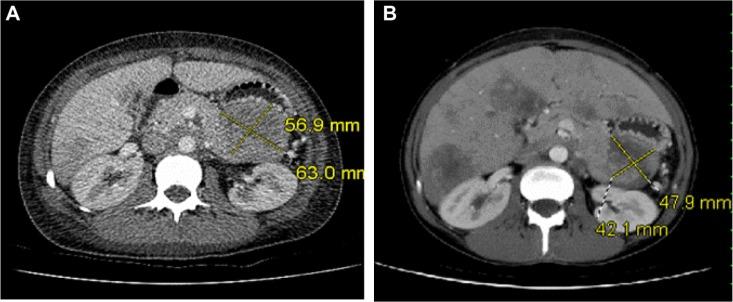

To report the case of a 28-year-old woman who presented with hypercalcemia (total calcium =4.11 mmol/L), elevated parathyroid hormone (PTH) 24.6 pmol/L, normal parathyroid hormone-related peptide 7.8 pg/mL, and a 63 mm × 57 mm, poorly differentiated neuroendocrine carcinoma (small-cell type) pancreatic mass with liver metastases.

The pancreatic mass (56 mm × 49 mm) and metastases decreased in size with chemotherapy and calcium levels normalized. Eight months later, calcium increased to 3.23 mmol/L, PTH increased to 48.2 pmol/L, and the pancreatic mass increased in size to 67 mm × 58 mm. The patient was given a trial of cinacalcet but was unable to tolerate it. Chemotherapy was restarted and resulted in a decrease in the pancreatic mass (49 mm × 42 mm), a reduction in PTH levels (16.6 pmol/L), and calcium levels (2.34 mmol/L).